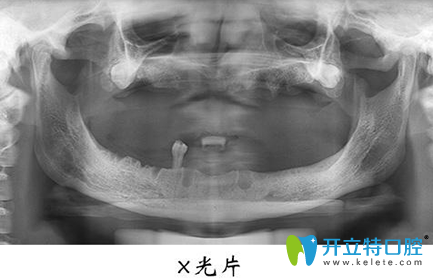

宏沅膛口腔面診的醫(yī)生非常細(xì)心也很有耐心,我不懂的牙齒問(wèn)題都會(huì)很有耐心的告知我,在牙齒種植術(shù)前,需要進(jìn)行常規(guī)的身體檢查,拍攝X光片,了解失牙區(qū)的骨質(zhì)和骨量,以確定是否適宜進(jìn)行牙齒種植等…